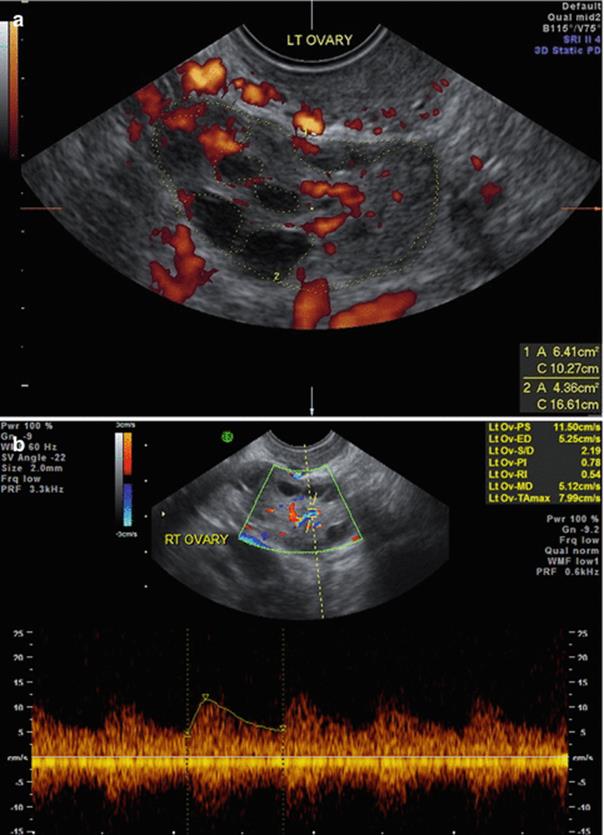

Fig. 2.3

(a, b) Stromal blood flow

Stromal Blood Flow (Fig. 2.3a, b)

· Stromal Flow Index (FI) [6]

· <11 low responder

· 11–14 Normal responders

· >15 risk of OHSS

· Stromal Peak Systolic Velocity (PSV)

· Low stromal PSV in the early follicular phase predicts poor responders

· Increased stromal PSV with unchanged resistance predicts increased risk of OHSS